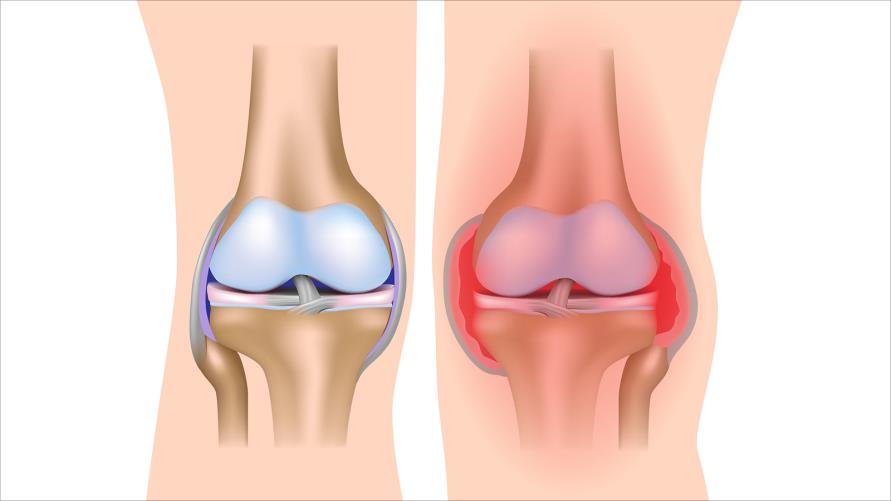

6 علاجات طبيعية لالتهاب المفاصل

علاج التهاب المفاصل الروماتيزي هو مرض التهابي مزمن يؤثر على الملايين حول العالم. لذلك، يسبب هذا المرض ألمًا كبيرًا في…